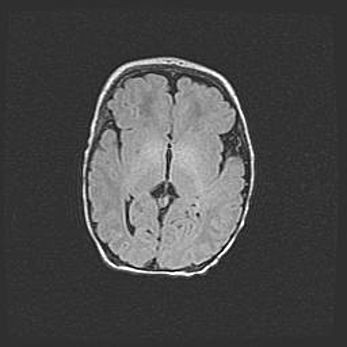

Множественные кисты обоих полушарий головного мозга, наибольшая из них в правой затылочной области. Ассиметричная атрофическая гидроцефалия.

Возраст: 7 месяцев

Вес: 5660 г

Пол: мужской

Окружность головы: 41,5 см

Срок гестации: 28-29 недель

Кисты головного мозга развиваются в результате многоочаговых некрозов вещества мозга и возникают вследствие перенесенной перинатальной инфекции, менингитов, энцефалитов, асфиксии, родовой травмы, расстройств мозгового кровообращения различного генеза. Образованию кист в веществе головного мозга плодов и новорожденных способствуют такие факторы, как высокое содержание в нем воды, недостаточная (или отсутствие) миелинизация и слабая астроглиальная реакция на повреждение.

Кисты могут сочетаться с гидроцефалией и другими поражениями головного мозга.